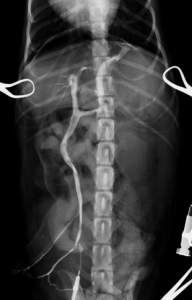

シャント血管を確認後、絹糸にて仮遮断し、門脈圧の過剰な上昇がないことを門脈圧測定にて確認後、完全結紮を行いました。

完全結紮後の門脈造影検査:シャント血管の遮断が確認され、血液が完全に肝臓にいっていることが確認されました。